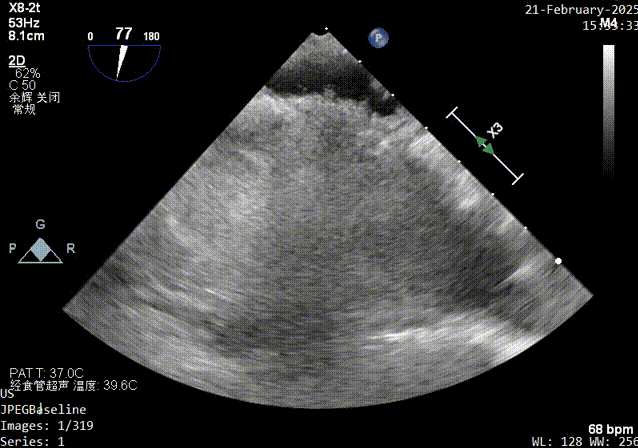

术前发泡实验超声影像

Xplane超声影像

主动脉短轴切面超声影像